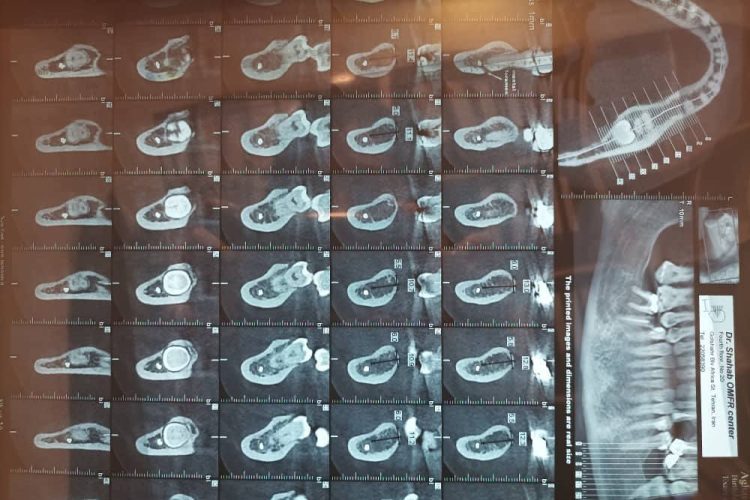

گزارش کاشت ۱۶ واحد ایمپلنت برند DPI

آرشیو جراحی

زهرا عباسیان 1403-03-29 0 دیدگاه